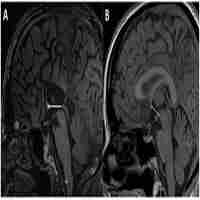

| Abstract | OBJECTIVE The corpus callosum is the major commissure connecting the cerebral hemispheres. Prior evidence suggests involvement of the corpus callosum in the pathophysiology of Tourette's disorder. The authors assessed corpus callosum size and anatomical connectivity across the cerebral hemispheres in persons with Tourette's disorder. METHOD The size of the corpus callosum was determined on the true midsagittal slices of reformatted, high-resolution magnetic resonance imaging scans and compared across groups in a cross-sectional case-control study of 158 subjects with Tourette's disorder and 121 healthy comparison subjects, ages 5-65 years. RESULTS In the context of increasing midsagittal corpus callosum area from childhood to age 30 years, children with Tourette's disorder had smaller overall corpus callosum size, whereas adults with Tourette's disorder on average had larger corpus callosum size, yielding a prominent interaction of diagnosis with age. Corpus callosum size correlated positively with tic severity. Corpus callosum size also correlated inversely with dorsolateral prefrontal and orbitofrontal cortical volumes in both the subjects with Tourette's disorder and the comparison subjects, but the magnitudes of the correlations were significantly greater in the group with Tourette's disorder. The effects of medication and comorbid illnesses had no appreciable influence on the findings. CONCLUSIONS Given prior evidence for the role of prefrontal hypertrophy in the regulation of tic symptoms, the current findings suggest that neural plasticity may contribute to smaller corpus callosum size in persons with Tourette's disorder, which thereby limits neuronal trafficking across the cerebral hemispheres and reduces input to cortical inhibitory interneurons within the prefrontal cortices. Reduced inhibitory input may in turn enhance prefrontal excitation, thus helping to control tics and possibly contributing to the cortical hyperexcitatibility reported previously in patients with Tourette's disorder. |